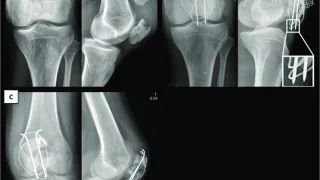

手術日+555日目 2025/9/5(金)(膝蓋骨骨折の再手術)

午前の病院での仕事と脆弱性骨盤骨折の患者台風15号の影響で, 朝からしとしとと雨. 気温は25 ℃に届かず, ようやく秋の気配を感じる涼しい朝でした.8時前に病棟に上がり, 昨日, 後輩医師が執刀した2人の若い患者さんの術後経過を確認しまし...